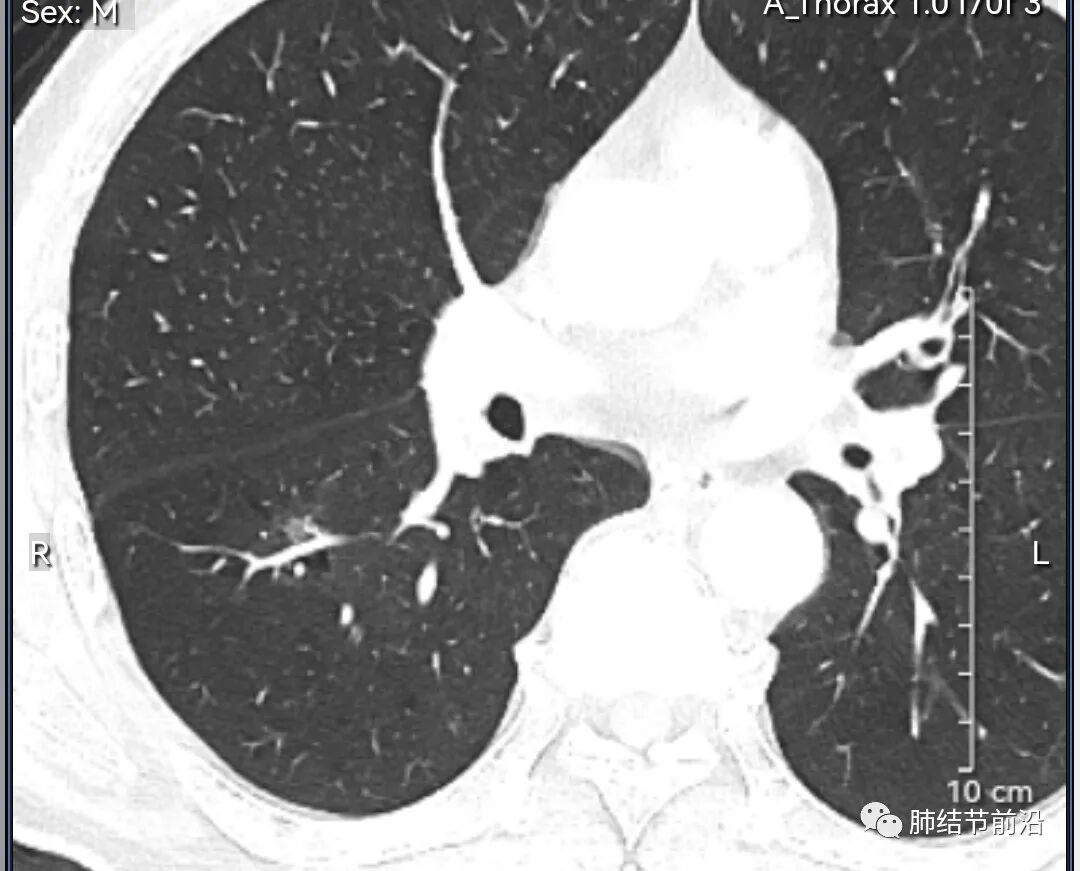

男性,67岁,重度吸烟史。CT发现右下肺囊腔。来看一下这个CT的特点:

该囊腔形态非常有特点,和常见的圆形肺大泡有很大的区别。

1.囊腔中央实性成分,周围有磨玻璃影。

2.囊腔中央有血管。

3.囊腔外周有分叶形态。

4.囊腔有胸膜牵拉。

出现这几种形态,CT可以确认恶性的腺癌。这个囊腔形成的机制,为肿瘤实性成分堵塞细支气管形成活瓣,肺泡内压力增高破裂行成,因此肺内血管成分保留。由于肺泡压力增高,而呈分叶状。另外,也有肿瘤的胸膜牵拉这一特点。

囊腔周围磨玻璃+囊腔中央血管为特征性表现。如果持续存在,几乎可以100%确认为早期肺腺癌。